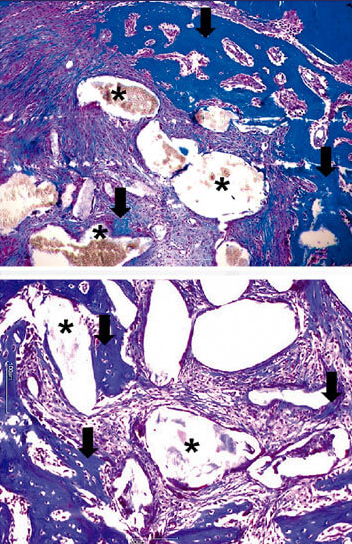

Fotomicrografias representativas da área de osso neoformado (15 dias após implante do material)

Tecido ósseo neoformado (seta); Partículas do biomaterial(*). (Coloração: TM).